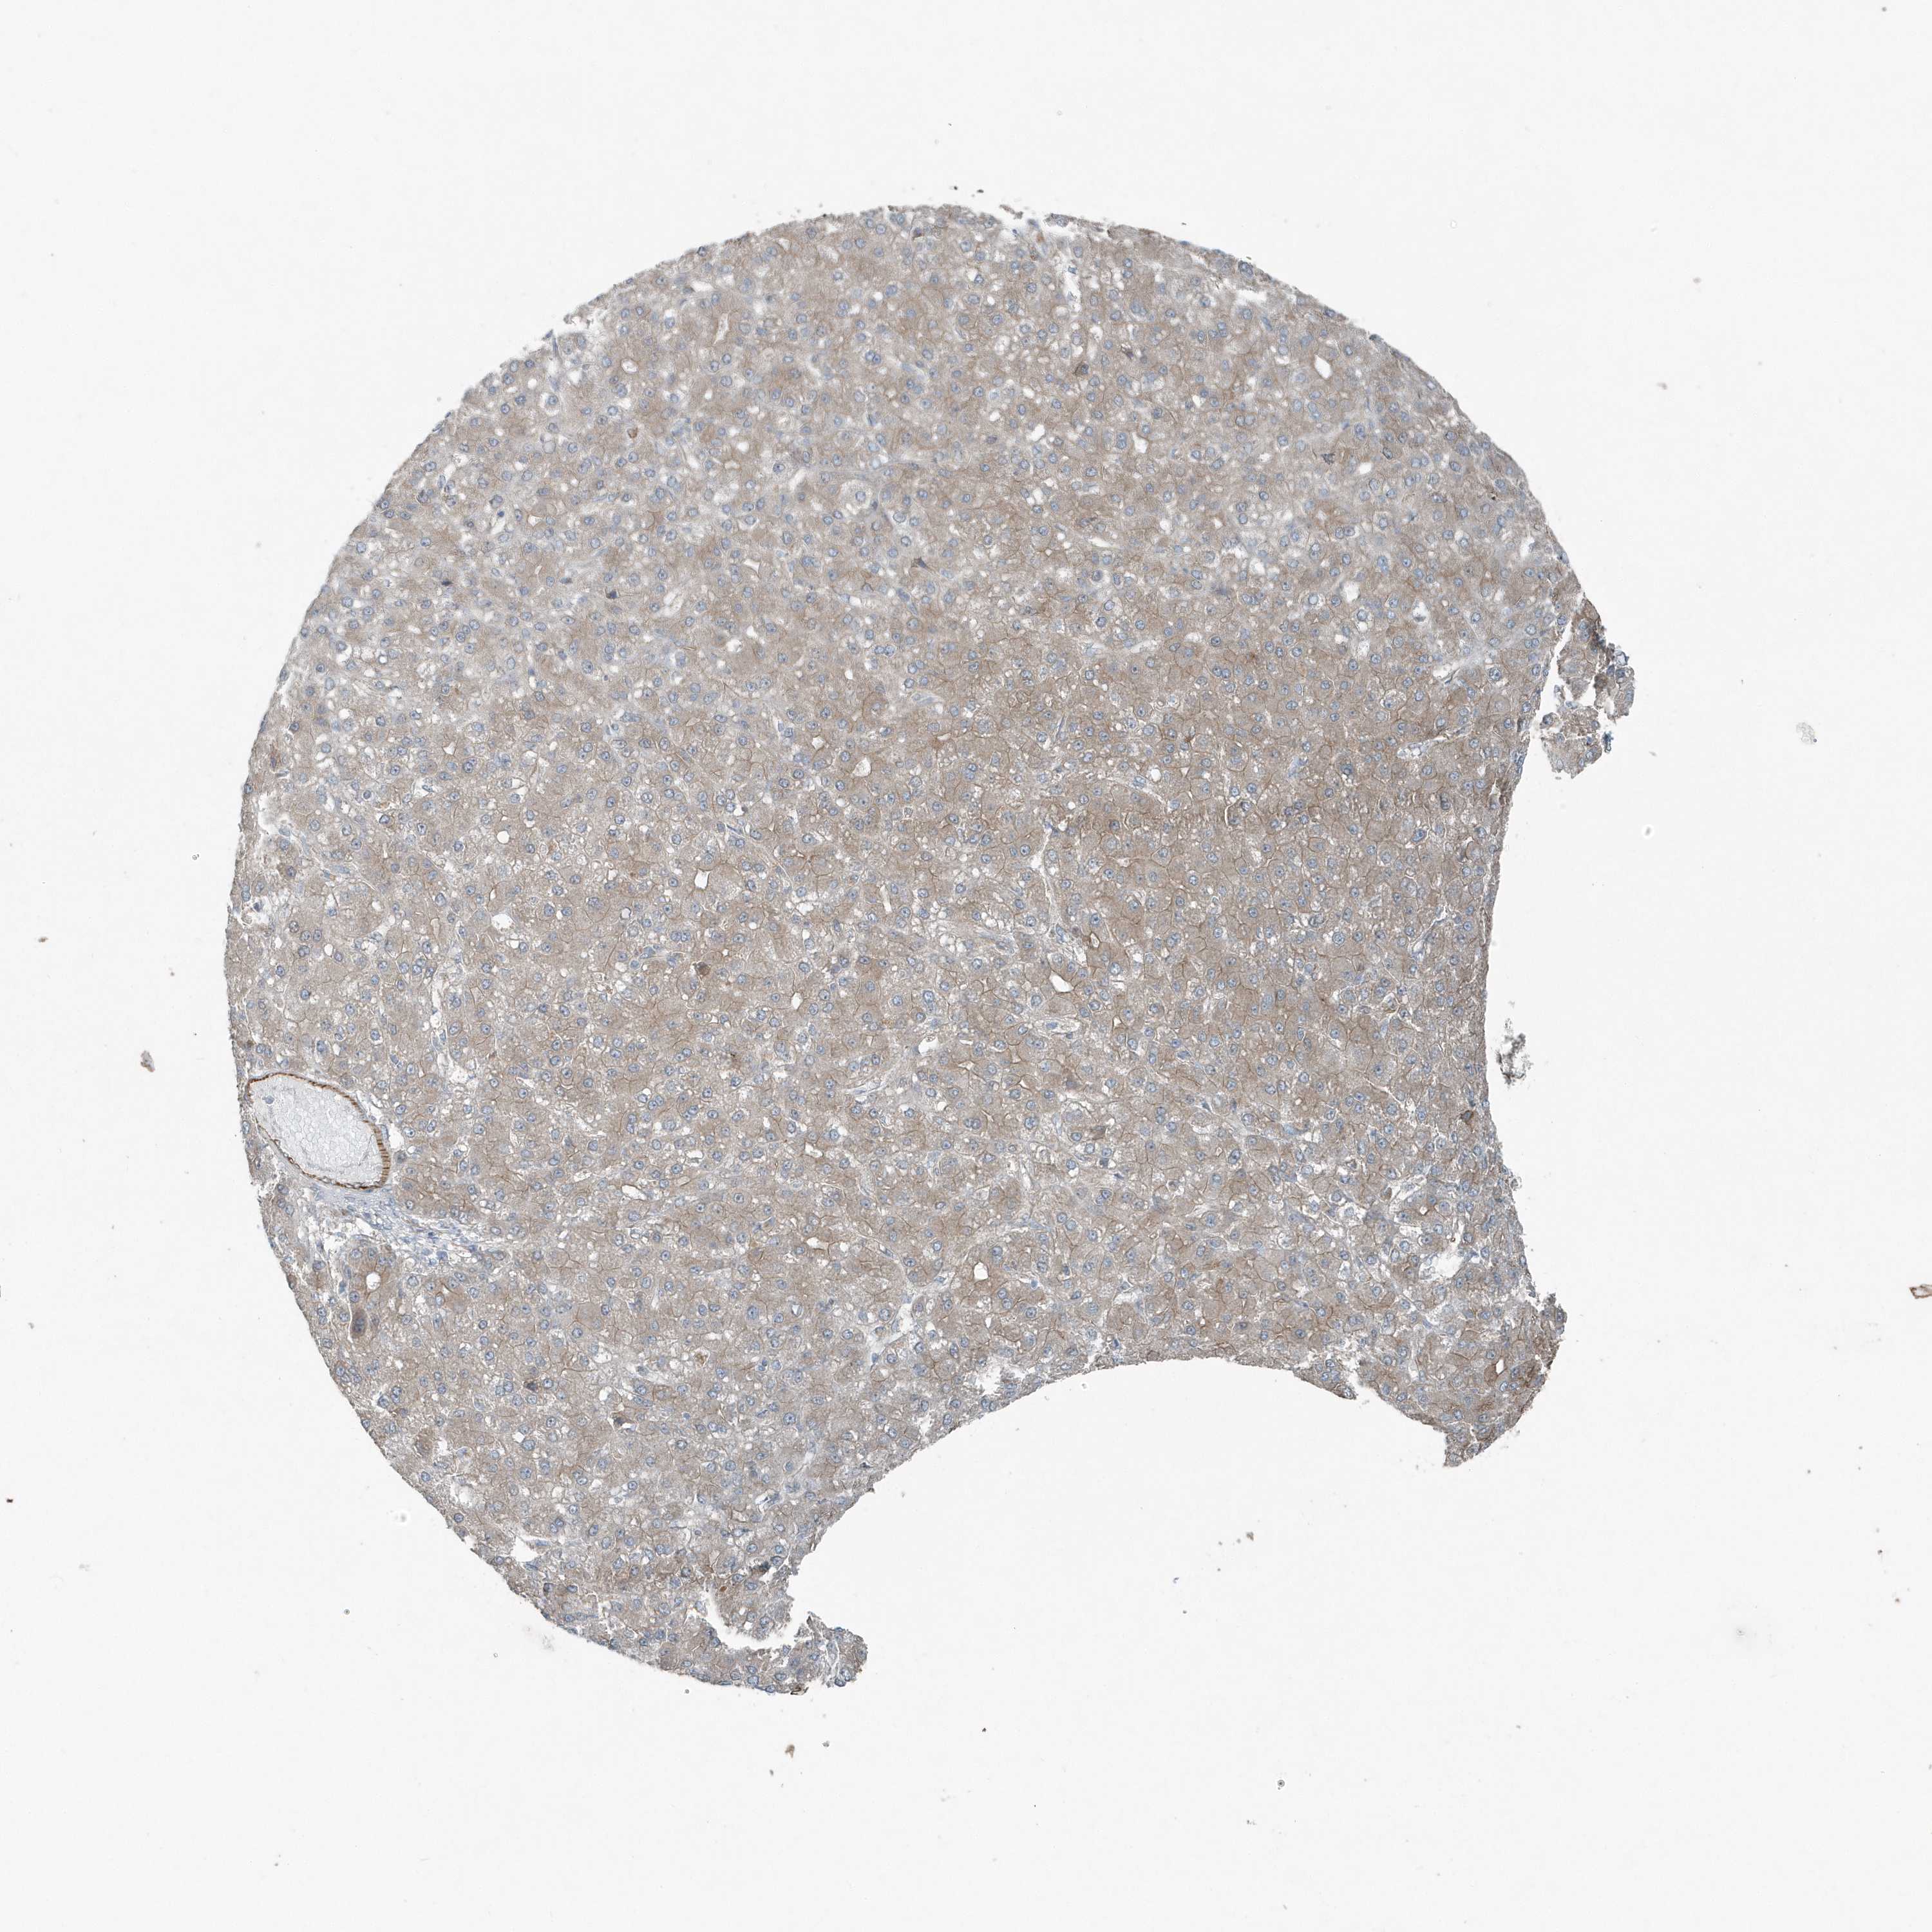

LIVER CANCER - Protein expressioni

A mouse-over function shows sample information and annotation data. Click on an image to view it in a full screen mode. Samples can be filtered based on level of antibody staining by selecting one or several of the following categories: high, medium, low and not detected. The assay and annotation is described here.

Antibody stainingi

Antibody staining in the annotated cell types in the current human tissue is reported as not detected, low, medium, or high, based on conventional immunohistochemistry profiling in selected tissues. This score is based on the combination of the staining intensity and fraction of stained cells.

Each image is clickable and will lead to virtual microscopy that enables deeper exploration of all samples and also displays staining intensity scores, fraction scores and subcellular localization as well as patient and tissue information for each sample.

Antibody HPA035849

Antibody HPA035850

Staining

High

Medium

Low

Not detected

Intensity

Strong

Moderate

Weak

Negative

Quantity

>75%

75%-25%

<25%

None

Location

Nuclear

Cytoplasmic/membranous

Cytoplasmic/membranous,nuclear

Cholangiocarcinoma

Carcinoma, Hepatocellular, NOS